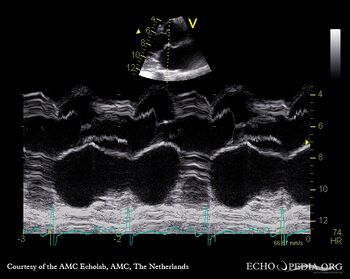

M-Mode through aortic valve PLAX: Color Doppler signal shows severe aortic regurgitation